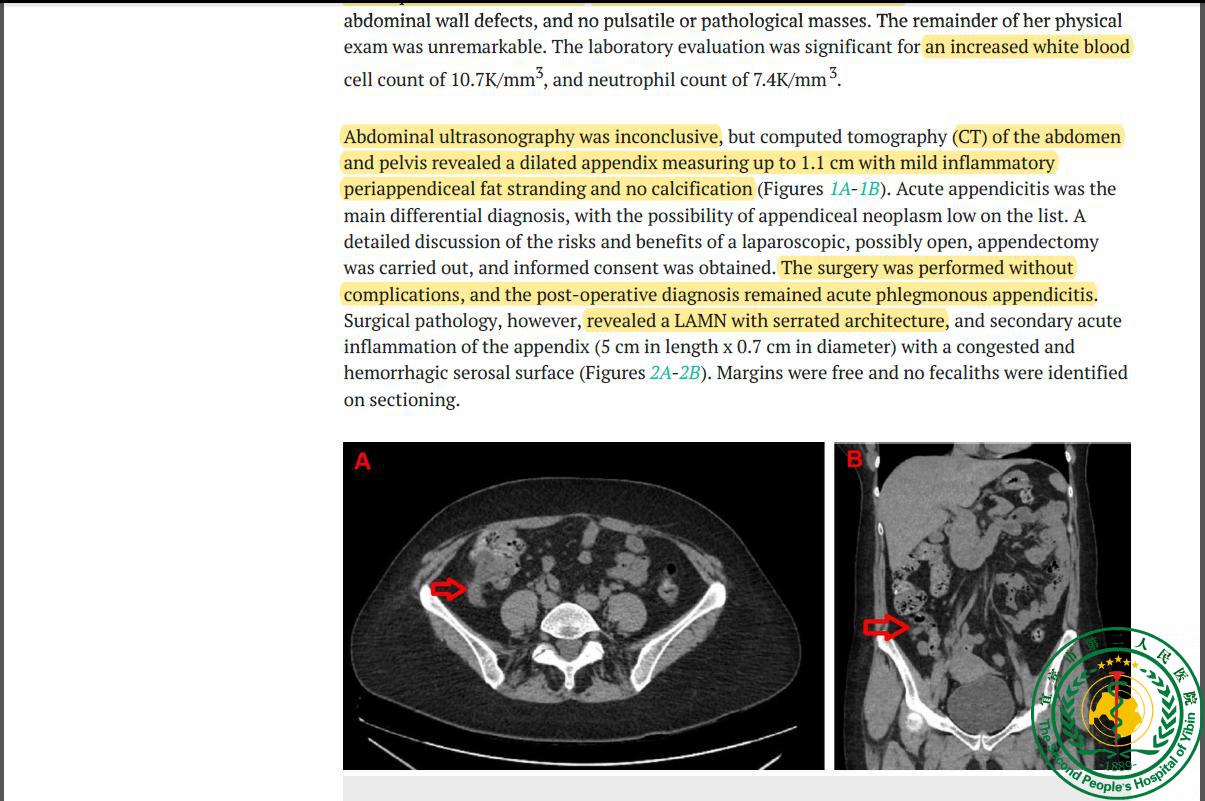

Low-grade Appendiceal Mucinous Neoplasm in the Context of Acute Appendicitis21677